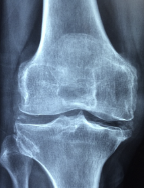

무릎 인공관절이란 무릎 관절의 연골이나 뼈가 심하게 손상되어 통증이나 기능장애가 있는 환자들에게 수술적으로 삽입하는 인공적인 관절입니다. 무릎 인공관절은 금속과 플라스틱으로 만들어져 있으며, 마모된 무릎 관절의 일부나 전체를 대체합니다.

무릎 인공관절이 필요한 경우는 주로 **퇴행성 관절염** 때문입니다. 퇴행성 관절염은 연령이나 과도한 운동, 외상, 비만 등의 원인으로 인해 연골이 점차 닳아가는 질환입니다. 연골은 뼈와 뼈 사이에 있는 부드러운 조직으로, 뼈의 마찰을 줄여주고 충격을 흡수하는 역할을 합니다. 연골이 닳으면 뼈와 뼈가 직접 부딪치게 되어 통증이나 염증, 관절의 변형이 발생합니다.